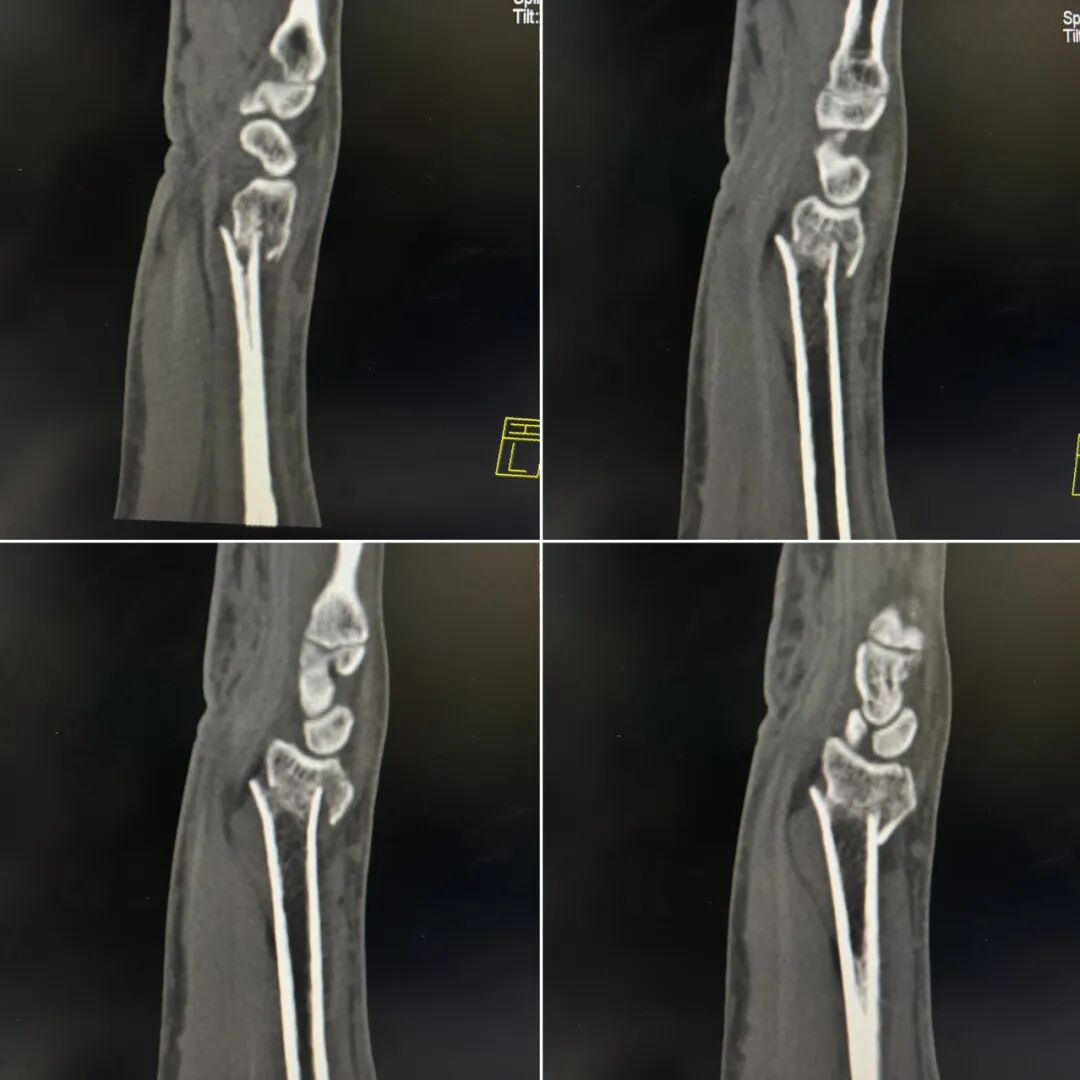

复位后复查X线:可见骨折端对位对线良好。

复位后要注意:

1.手指活动是否正常、有无麻木。

2.骨折外观畸形是否纠正

3.触摸骨折端是否还存在“台阶”